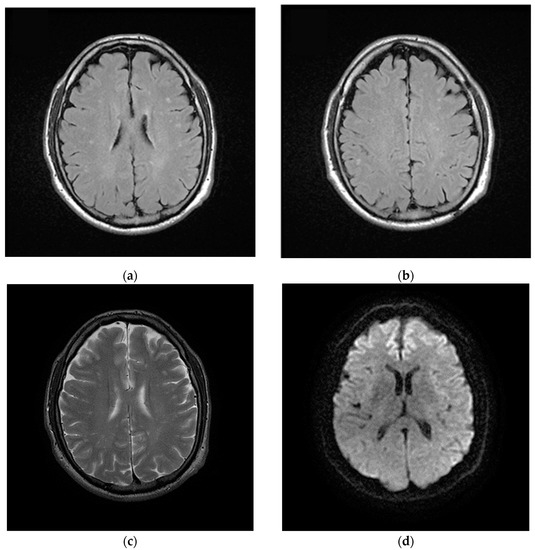

2.2. Post Hospital Phase